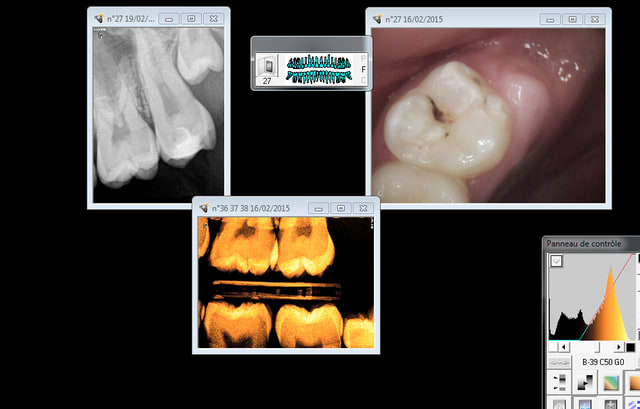

Et un autre. Ca paye la prévention hein yobi ! -)))) par contre si tu attends que la carie se développe et que tu dois faire 4 anesthésies sur le gamin pour le soigner tu es dans la merde.